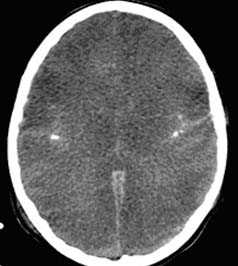

Применение компьютерной томографии в нейротравматологии существенно изменило представление о возможностях диагностики различных черепно-мозговых повреждений. КТ является в настоящий момент «золотым стандартом» - наиболее информативным методом обследования больных с черепно-мозговыми травмами и позволяет в самые короткие сроки судить о механизмах возникновения поражения мозга, его характере, распространенности, выраженности отека и дислокации мозга, а также динамике этих изменений.

- выявить наличие внутричерепной гематомы (её характер, локализацию, размеры),

- выявить субарахноидальное кровоизлияние,

- выявить внутрижелудочковую гематому,

- выявить наличие пневмоцефалии.